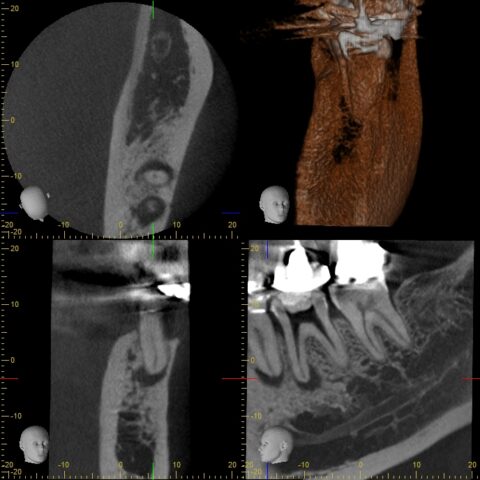

治療設備についても、歯科用CT、マイクロスコープ、iTeroなどを導入し、精密で再発の少ない治療提供に努めています。